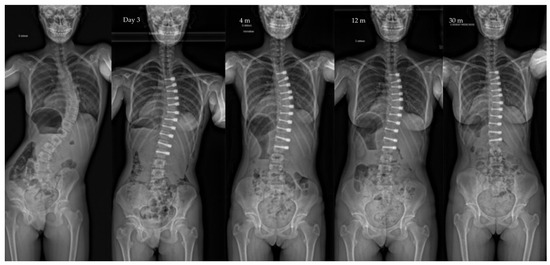

| Pre-op | Post-op Day 3 | Post-op 1y | Last f/u | p-Value | |

| Major curve | 49°(8,9°) | 27°(12°) | 22°(12°) | 19°(14°) | <0.01 |

| Secondary curve | 27°(14°) | 23°(15°) | 22°(11°) | 17°(10°) | <0.01 |

| Instrumented curve | NA | 26°(11°) | 23°(10°) | 20°(14°) | <0.01 |

| Kyphosis (T1–T12) | 20°(13°) | 23°(13°) | 25°(12°) | 24°(14°) | 0.06 |

| Lordosis (L1–L5) | 36°(12°) | 32°(13°) | 40°(7°) | 40°(8°) | 0.07 |